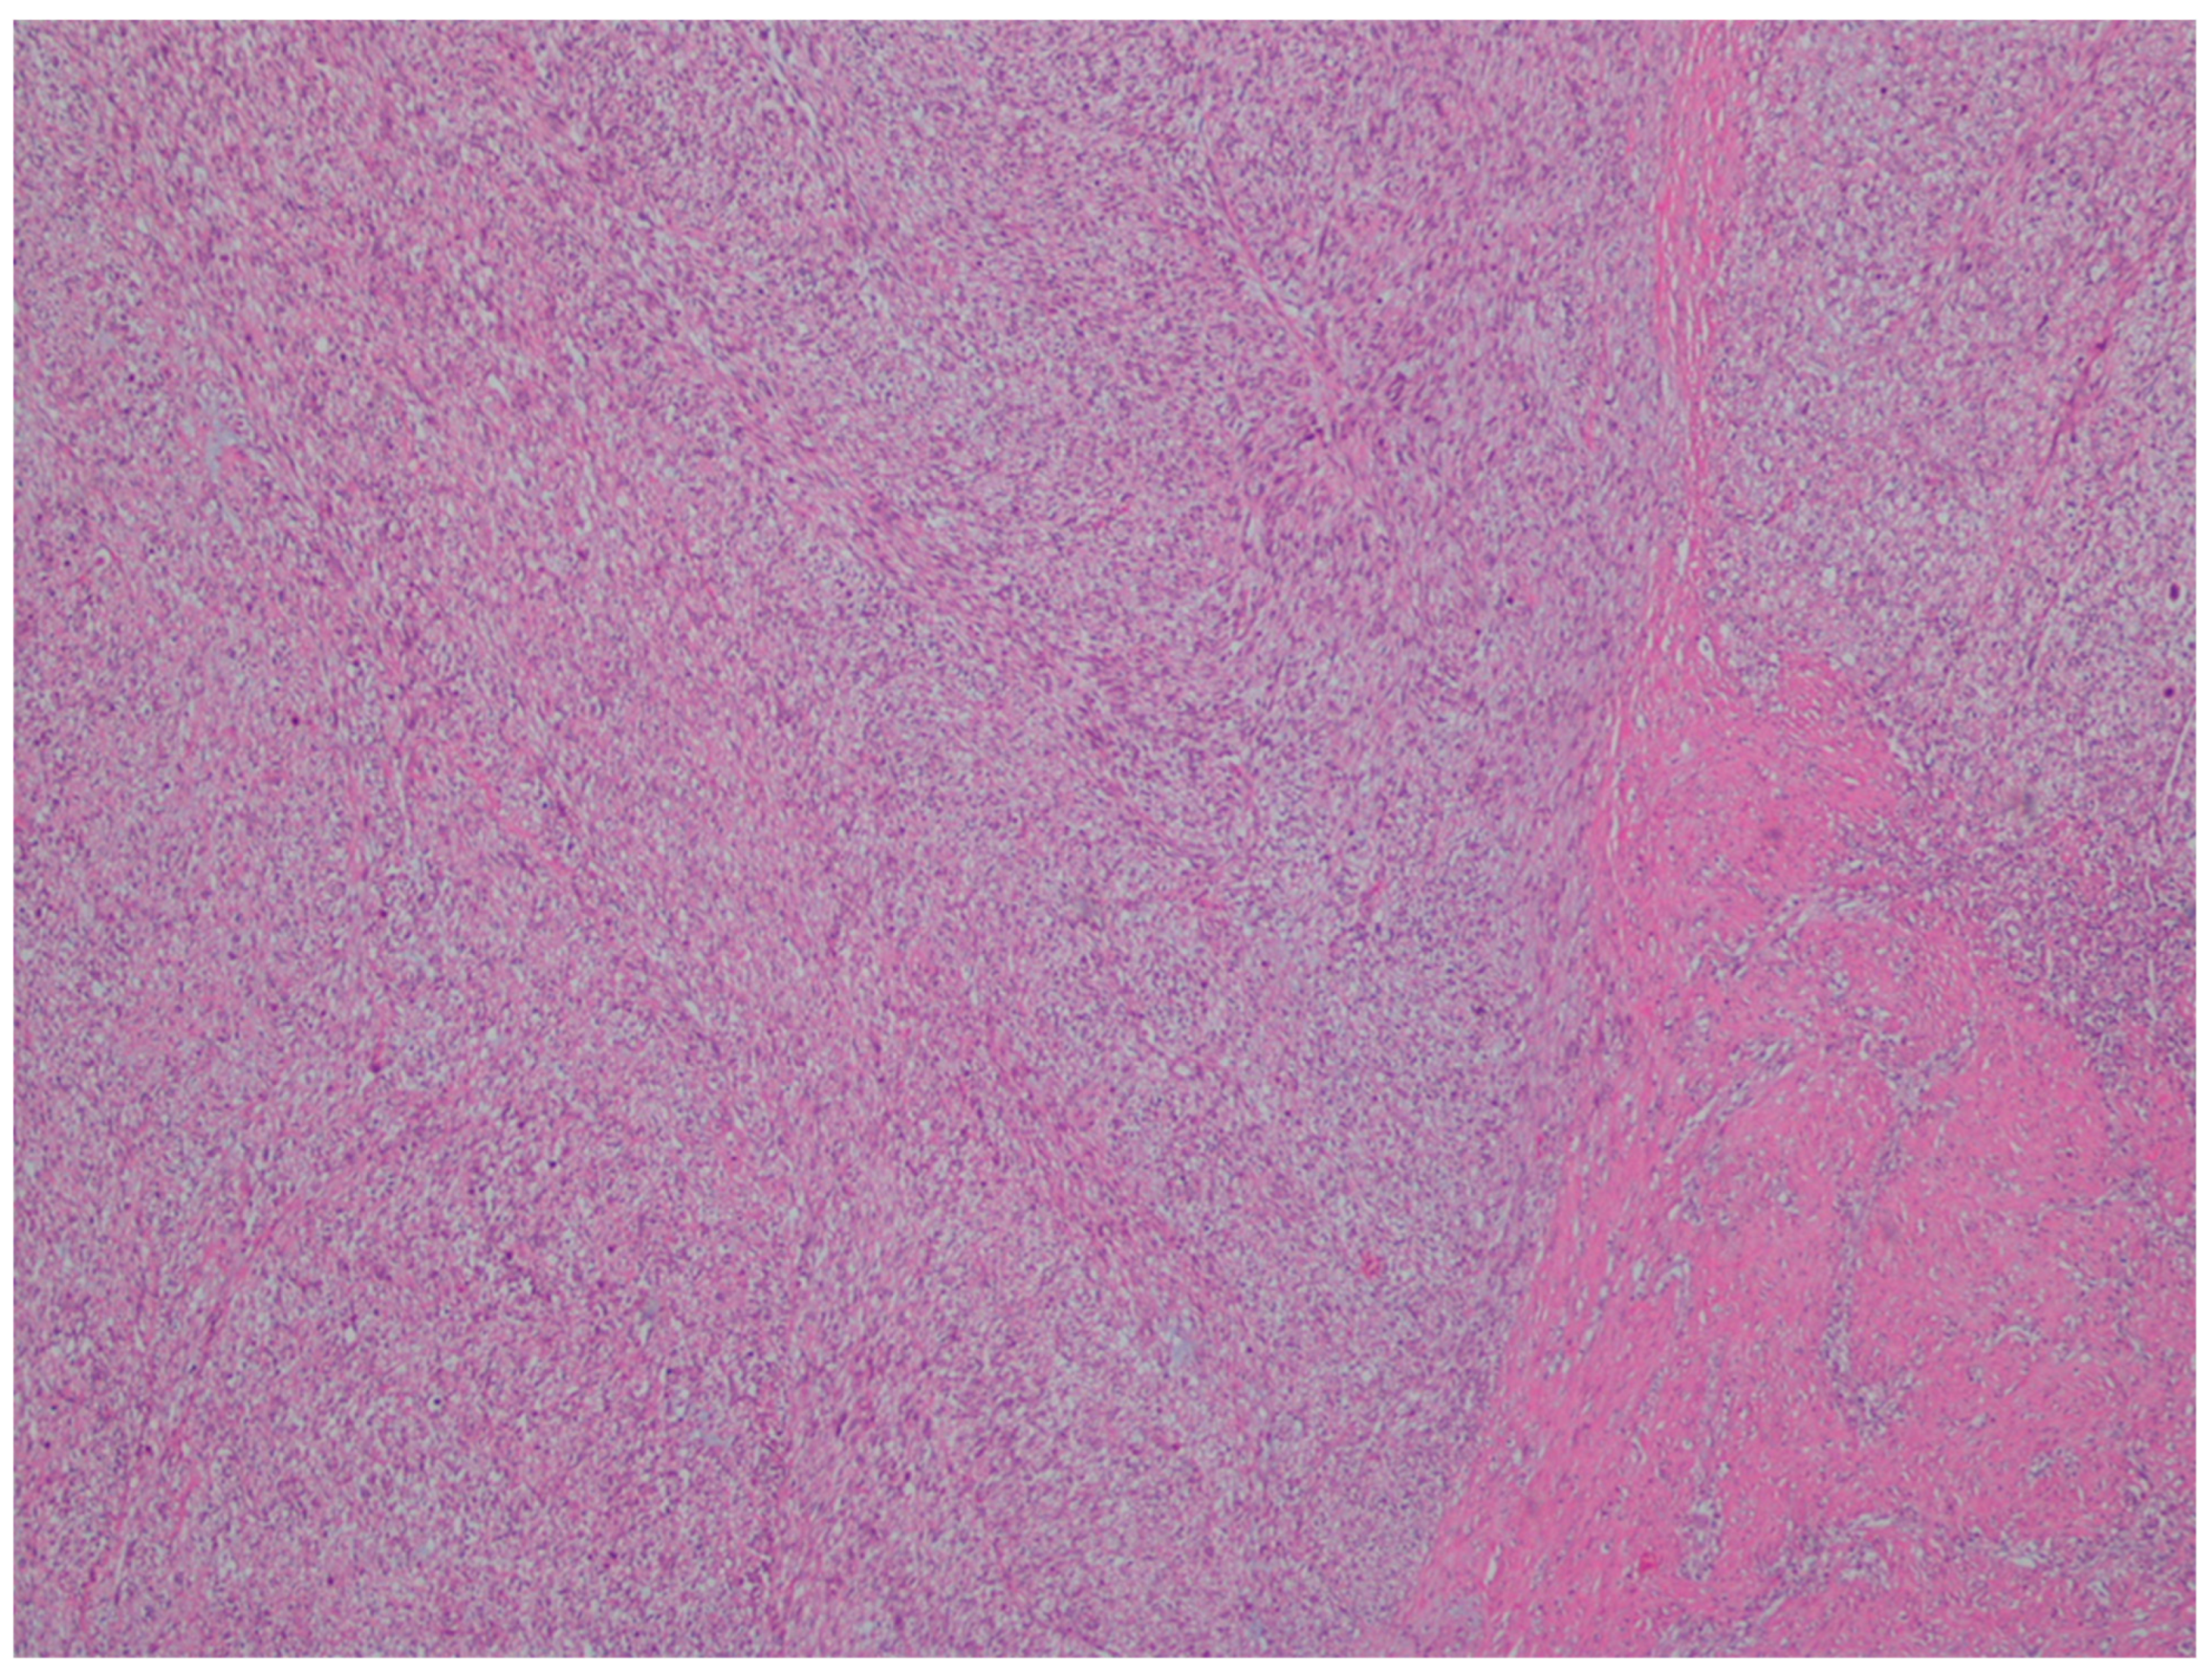

| Fibromatosis | 30 and 40 years | Mesentery of the small bowel | Abdominal pain | Long fascicles of spindle cells with ovoid nuclei without atypia or necrosis | Β-catenin |